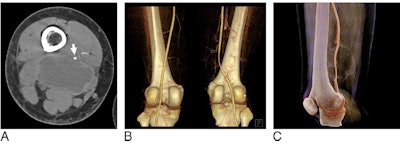

Seeking alternative visualization methods to confirm tumor invasion, Li and colleagues acquired the CTA scans of 43 patients who presented to the hospital with a deep soft-tissue sarcoma in one of their extremities between January 2013 and June 2016. The researchers reconstructed these scans with two techniques: traditional 3D volume rendering and cinematic rendering (syngo.via VB10, Siemens Healthineers).

The radiologists were able to identify tumors invading major vessels on the cinematically rendered CT scans with nearly the same accuracy as on the CTA and volume-rendered scans. There were no statistically significant differences between the three techniques.

In addition to matching the accuracy of the other methods, cinematic rendering provided a longer longitudinal view of the vessels and more photorealistic anatomic details, which helped optimize tumor visualization, according to the authors.